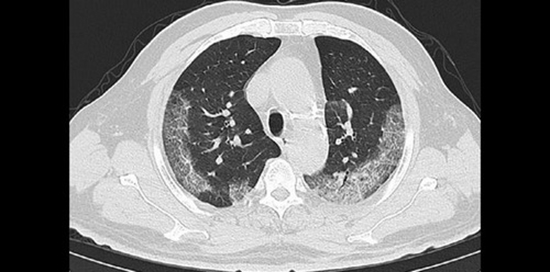

بررسی ارتباط بین اسکور درگیری سی تی اسکن قفسه سینه با علائم حیاتی و یافته های آزمایشگاهی در زمان مراجعه و نیاز به بستری، در بیماران مشکوک به درگیری ناشی از کووید19 مراجعه کننده به تریاژ تنفسی بیمارستان امام خمینی تهران در فروردین و اردیبهشت ماه سال ۱۳۹۹

ارتباط بین اسکور درگیری ct قفسه سینه با علائم حیاتی و یافته آزمایشگاهی کرونا